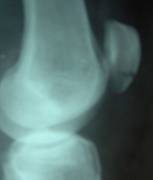

Radiografia simpla

incidente: AP, LL, oblice, speciale

de stres

comparativa